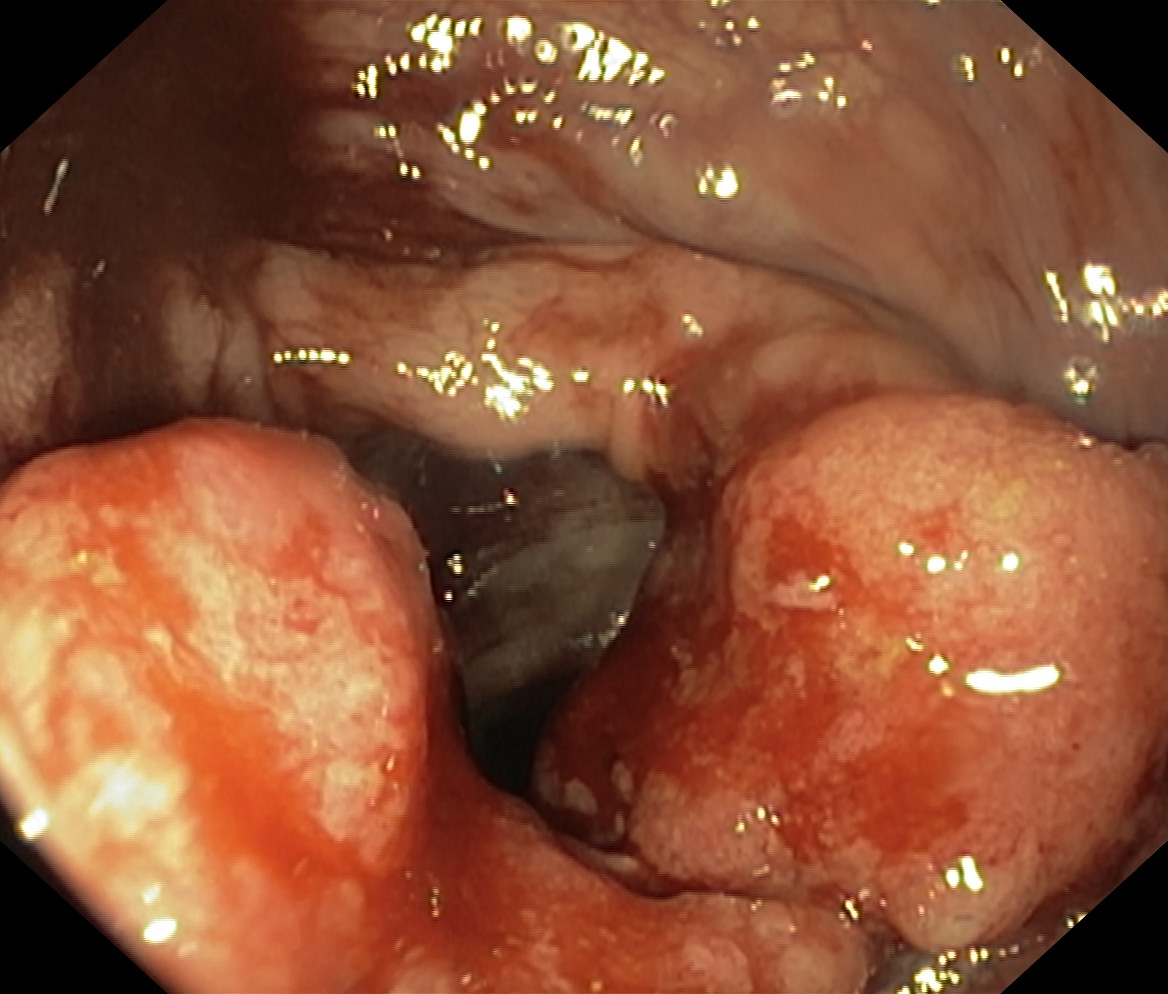

Nowotwory przewodu pokarmowego